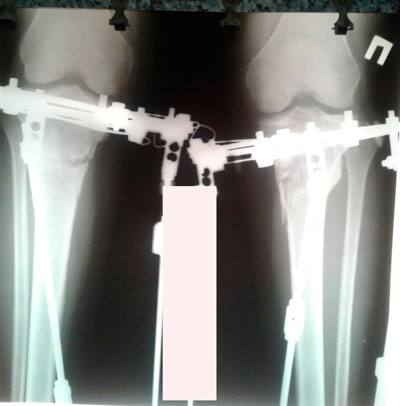

Дата операции - 04.03.2019г.

Дата снятия аппаратов - 18.06.2019г.

Срок сращения - 104 дня.

рентген перед снятием аппаратов.